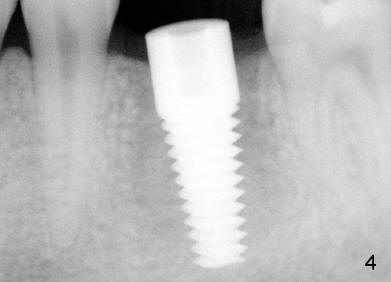

Fig.6 shows Emax crown with limited space for porcelain before cementation.  In fact, the crown was fractured during cementation at the area indicated by arrowhead in Fig.6.  A new crown was fabricated with core material used in the occlusal portion without porcelain overlay.  The new crown was then cemented without complication.

We did observe that the restoration did not mate with the implant body (Fig.6). The margin is to be prepared on the implant itself, overlapping the implant/abutment interface that will create a nice emergence profile while offering a strong bond between the surfaces. Without doing this, a couple things can happen:

Thank you very much for writing the detailed explanation.  Fig. 7 shows the die of this case.  The margin of the implant (arrowheads) is probably subgingival, as compared to the gingival margin of the neighboring teeth.

Black arrowheads in Fig.8 (solid cast) point to the implant margin, whereas white ones the junction of the abutment and the implant.  The ruler in the background indicates that the height of the abutment is no more than 3 mm.